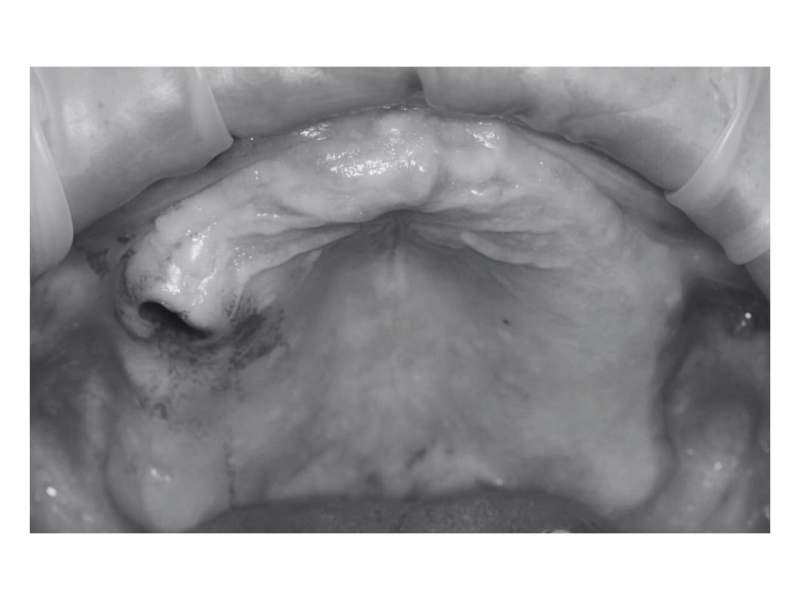

Одномоментная имплантация

Пациент 40 лет. Обратился к нам с жалобами на боли в области установленного ранее зубного протеза на верхней челюсти.

Пациенту сняли металлокерамический протез, после изучения дентальной КТ составили план лечения, в котором предполагалась установка дентальных имплантатов в области 642/1345 зубов с одномоментным временным протезированием.

Также одномоментно был произведен закрытый синус-лифтинг в области 6/5 зубов.

Временный протез был установлен на аппарате CAD CAM и установлен на второй день после имплантации.